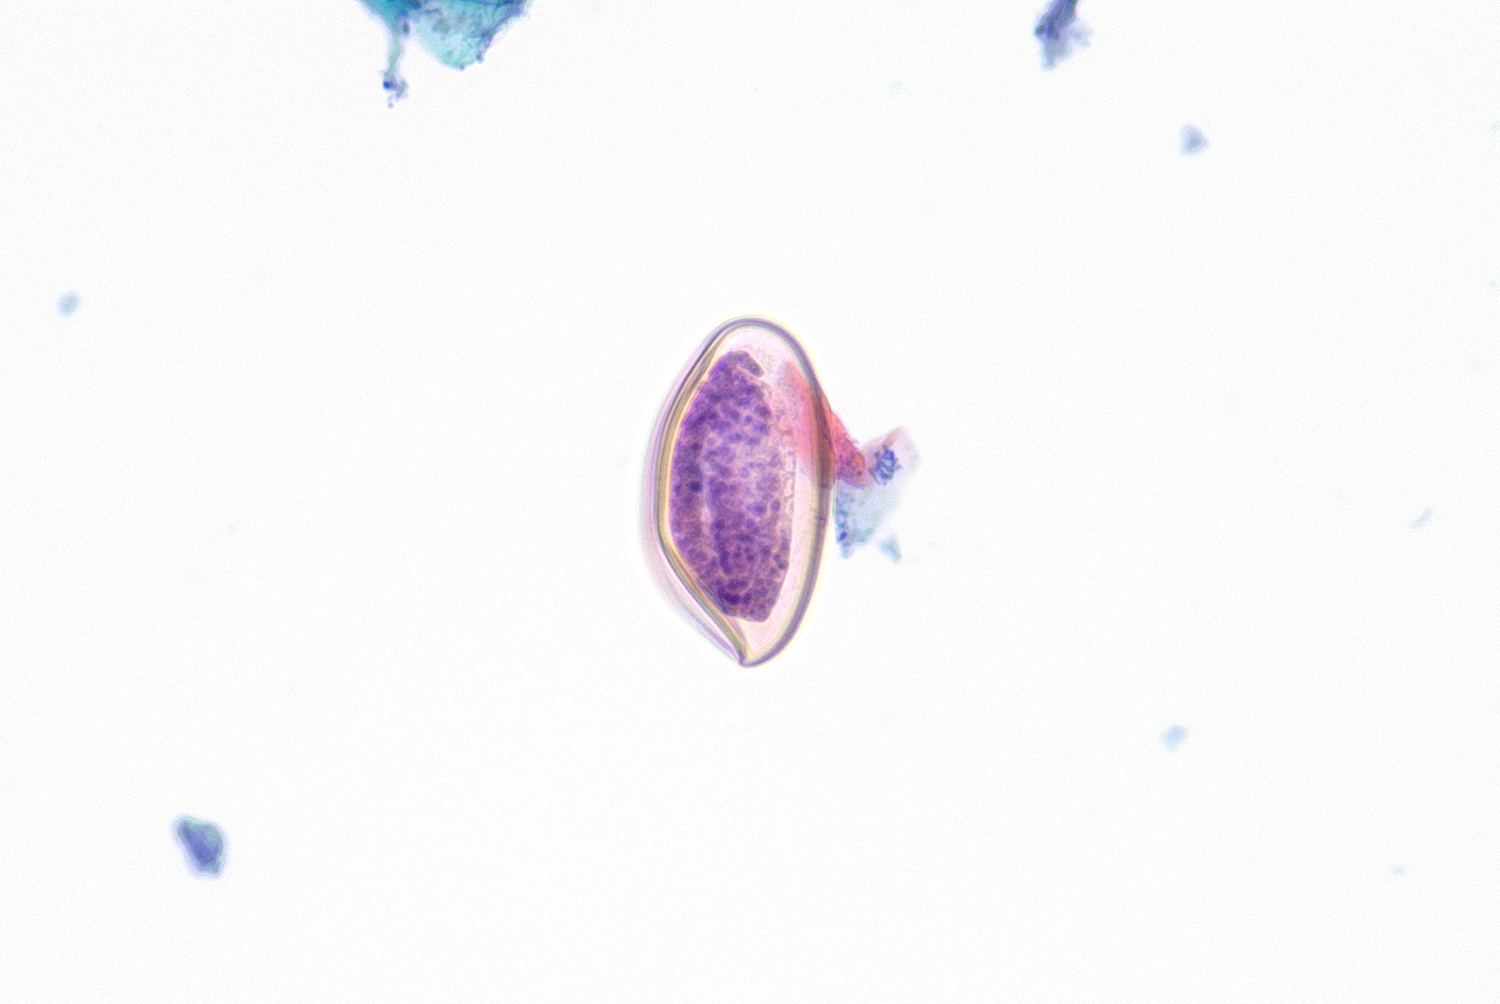

This week's case was generously donated by Dr. Tudo Rares Olariu, the head of the clinical laboratory at the Municipal Clinical Emergency Hospital in Timisoara, Romania. The following object was seen in a stool specimen from a child with multiple mucosanguineous stools. It measures approximately 45 micrometers in greatest dimension. What is your diagnosis?

Answer to Case 790

Answer to the Parasite Case of the Week 790: Rodentolepis (formerly Hymenolepis) nana egg.

This is a classic example of an R. nana egg showing the inner and outer membranes, oncosphere with large splayed hooklets, and polar thickenings from which filaments extend into the space between the oncosphere and outer membrane. It's hard to make out the polar filaments in this particular example, but the smaller size allows us to differentiate it from the larger Hymenolepis diminuta egg.

Interestingly, most readers on social media are still referring to this parasite as Hymenolepis nana. However, I can confirm that Rodentolepis is now the preferred genus. For further reading, I recommend the systematic study of hymenolepidid cestodes by Haukisalmi and colleagues which supports the split into separate genera for a more practical and stable classification.Monday, October 13, 2025